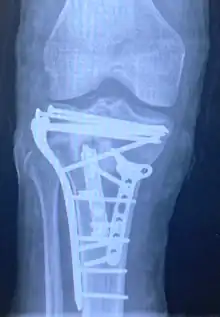

![]() | |

| A severe tibial plateau fracture with an associated fibular head fracture | |